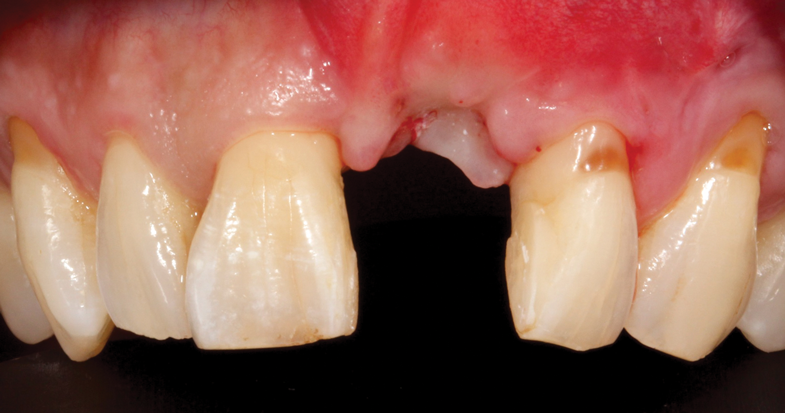

To demonstrate the principles and protocols described in this article, three case examples are included. The first case involves the treatment of a patient who sought replacement of the maxillary left canine (tooth No. 11) with an implant-supported restoration (Figure 11 through Figure 34), and in the second case, the patient presented for replacement of the maxillary left central incisor (tooth No. 9) (Figure 35 through Figure 44). In the third case, the patient also presented for replacement of the maxillary left central incisor (tooth No. 9) but had a preexisting bonded pontic made from the natural tooth. This was utilized in lieu of a composite tooth shell to fabricate the immediate provisional restoration. (Figure 45 through Figure 57).

(45.) A patient presented for the replacement of the maxillary left central incisor with a bonded pontic made from the natural tooth, which was removed.

Figure 45

(46.) Occlusal view of the implant after placement.

Figure 46